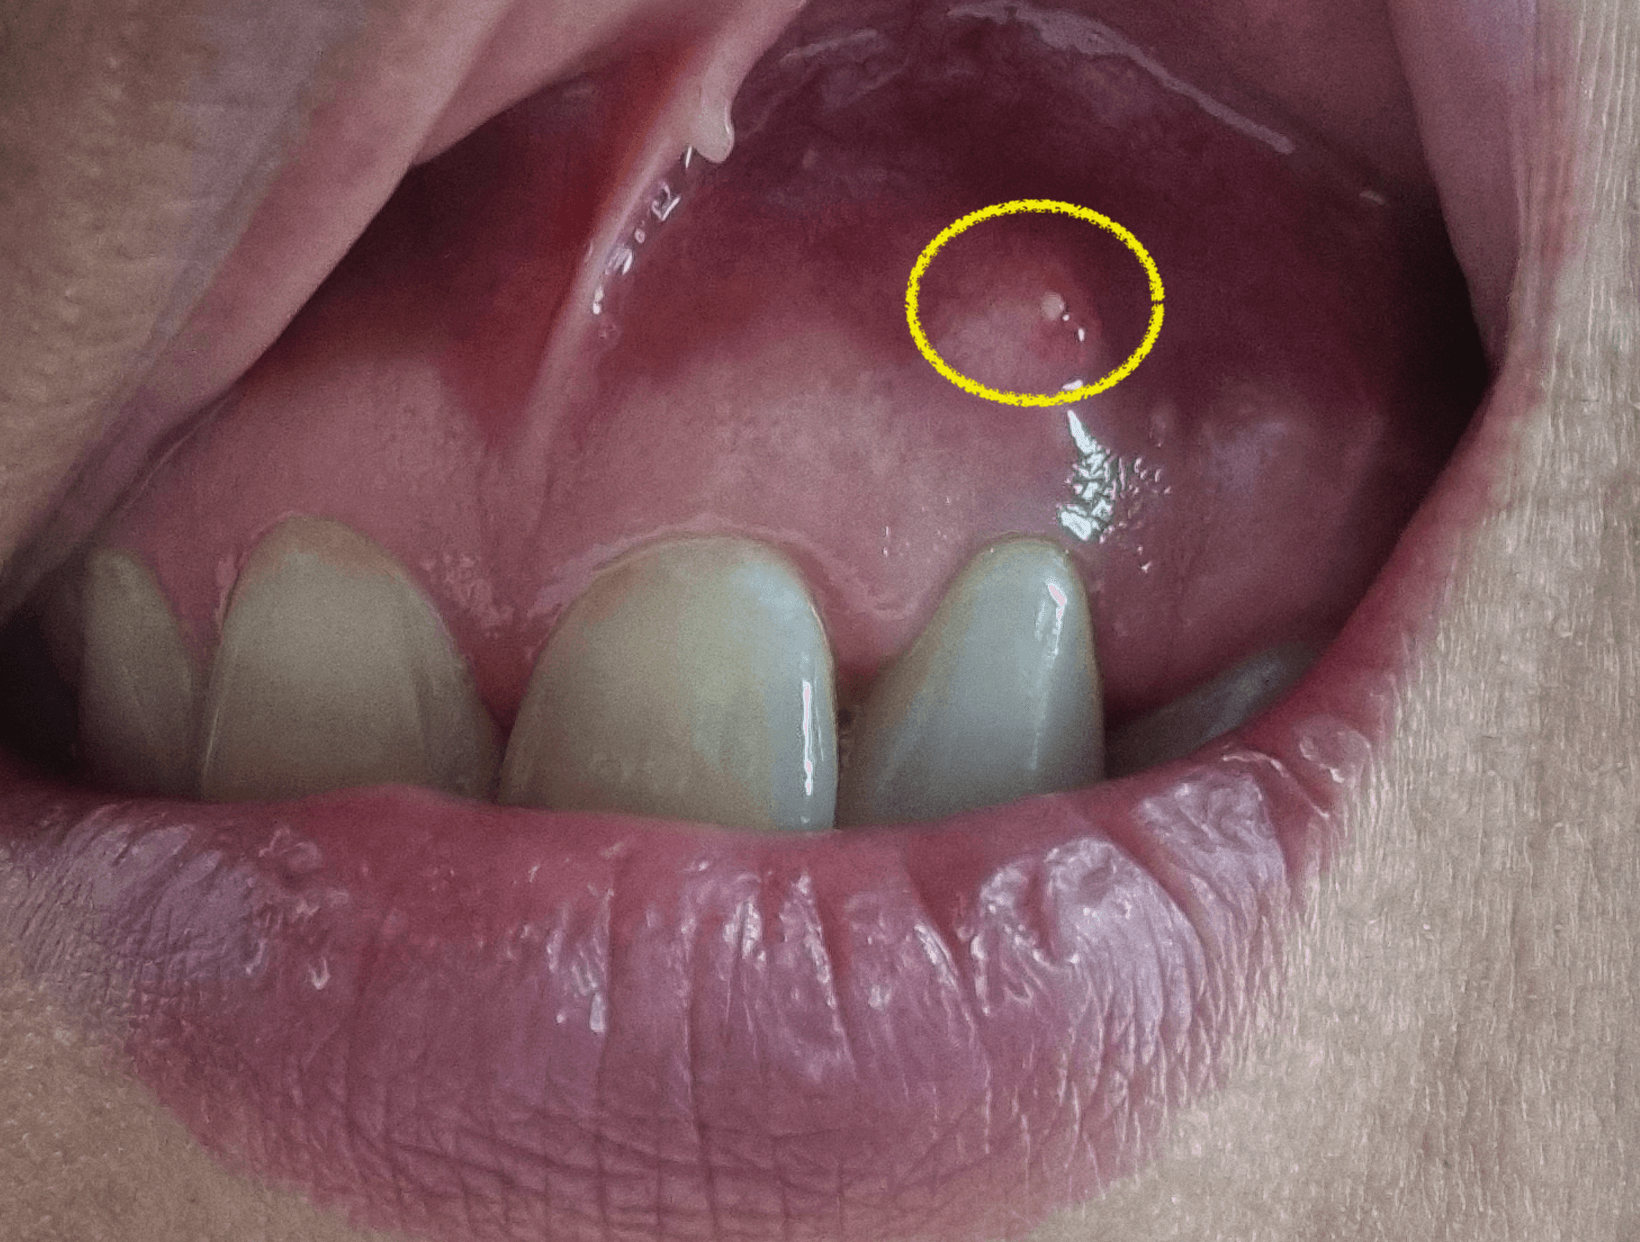

치근단절제술 수술을 한지 1년이 다된 지금 해당 앞니 치근단절제술을한 그부분에 잇몸이 다시 한번 불룩하게 티어 올라온것이 보였습니다. 그것은 딱봐도 염증이 차서 부어오른것이며, 저처럼 치근단절제술을 시행후 염증이 재발한 상황에 대한 내용을 의사가 아닌 환자로써 염증 재발 후기에 대한 정보를 공유 합니다.

1년정도 전에 치근단절제술을한 치아에서 다시 문제가 생겼습니다. 보통 3개월이 지나서 염증이 나오지 않으면 대부분 성공이라 생각하고 별일 없는이상 염증에 재발하지 않을거라 생각을 합니다.

그런데 저같은경우 기존에 염증 크기가 뼈이식을 할만큼 큰 낭종크기정도의 염증이라서 결국 염증이 완전하게 사라지지 않고 다시 다양한 사유로 인해 재발하게 된것 같다고 의사 선생님이 이야기를 했습니다.